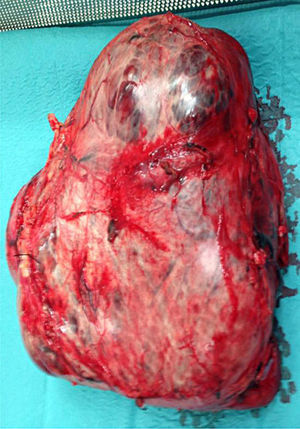

A 46-year-old patient with no medical history of interest came to our consultation complaining of postprandial fullness and a mass in the epigastrium (Fig. 1). Abdominal CT showed a large mass measuring 37cm×27cm×30cm situated between the left lobe of the liver, pancreas, kidney and splenic hilum (Fig. 2). There was a slight elevation in tumor markers: Ca 19.9 (80.8U/ml), and Ca 15.3 (85U/ml). We performed an en bloc resection of the mass, and the pathology study reported an eosinophilic variant of chromophobe cell carcinoma (Fuhrman nuclear grade 3) with extensive central necrosis (Fig. 3). This type of tumor is uncommon. The prognosis is good, with little tendency toward advancing or metastasizing, and with a 10-year survival rate of approximately 90%. The most important prognostic factors are tumor size, presence of sarcomatoid differentiation and tumor necrosis.